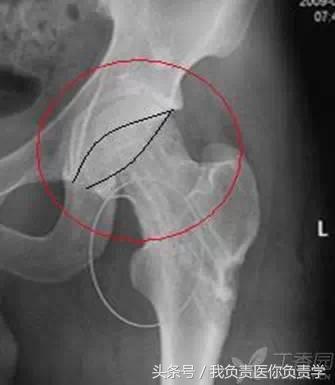

1.「交叉征」与髋关节撞击

在骨盆正位片上,髋臼前后缘线无交叉或在近端三分之一交叉,当髋臼后倾时,髋臼前后缘线出现交叉征象,即「交叉征」,此时容易发生髋臼与股骨头颈的撞击。常见于存在髋关节盂唇增生、髋关节置换前倾角不足的患者,怀疑此征时还应积极行其他影像学检查。